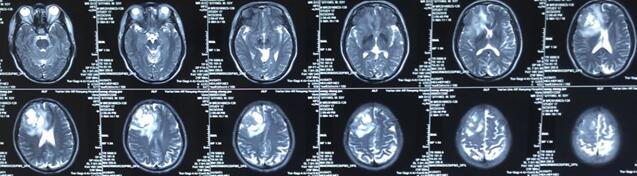

患者王某某,男,53歲,因“間斷頭痛半月”入神經(jīng)內(nèi)科十二病區(qū),發(fā)現(xiàn)顱內(nèi)占位后轉(zhuǎn)入神經(jīng)外科。既往患者有肺Ca病史,于一年前行手術(shù)治療。頭顱影像學(xué)診斷膠質(zhì)瘤?轉(zhuǎn)移瘤待排。2016年6月29日在3.0T磁共振定位后,劉增強副主任與其團隊為患者實施了立體定向腦內(nèi)病變活檢術(shù),此患者病灶為囊實性,手術(shù)難度較大,而一旦囊液流失則會發(fā)生腦組織漂移,導(dǎo)致靶點移位,因此手術(shù)計劃制定尤為重要,入顱點為右額部,穿刺后首先達到腫瘤實性部分,獲取病灶標本后,抽出部分囊液以緩解患者高顱壓癥狀,經(jīng)過精細的手術(shù)操作,最終成功獲取腫瘤標本,并且抽出約20ml腫瘤液,患者情況穩(wěn)定,術(shù)后兩小時即下床活動。

術(shù)后冰凍切片報告考慮轉(zhuǎn)移瘤,我院石蠟病理結(jié)果為少許低分化癌組織,結(jié)合病史符合肺癌腦轉(zhuǎn)移。